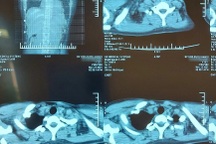

Theo bác sĩ Dũng, kết quả chụp CT ngực cho thấy khối u có đường kính hơn 5cm, bắt đầu chèn ép các tĩnh mạch chủ trên và động mạch chủ xung quanh. Nếu khối u tiếp tục phát triển sẽ cản trở máu từ tĩnh mạch chủ trên đi xuống, gây ra triệu chứng phù. Vì thế, cần phẫu thuật ngay thời điểm này để loại bỏ hoàn toàn khối u quái, tránh những rủi ro sức khỏe sau này.